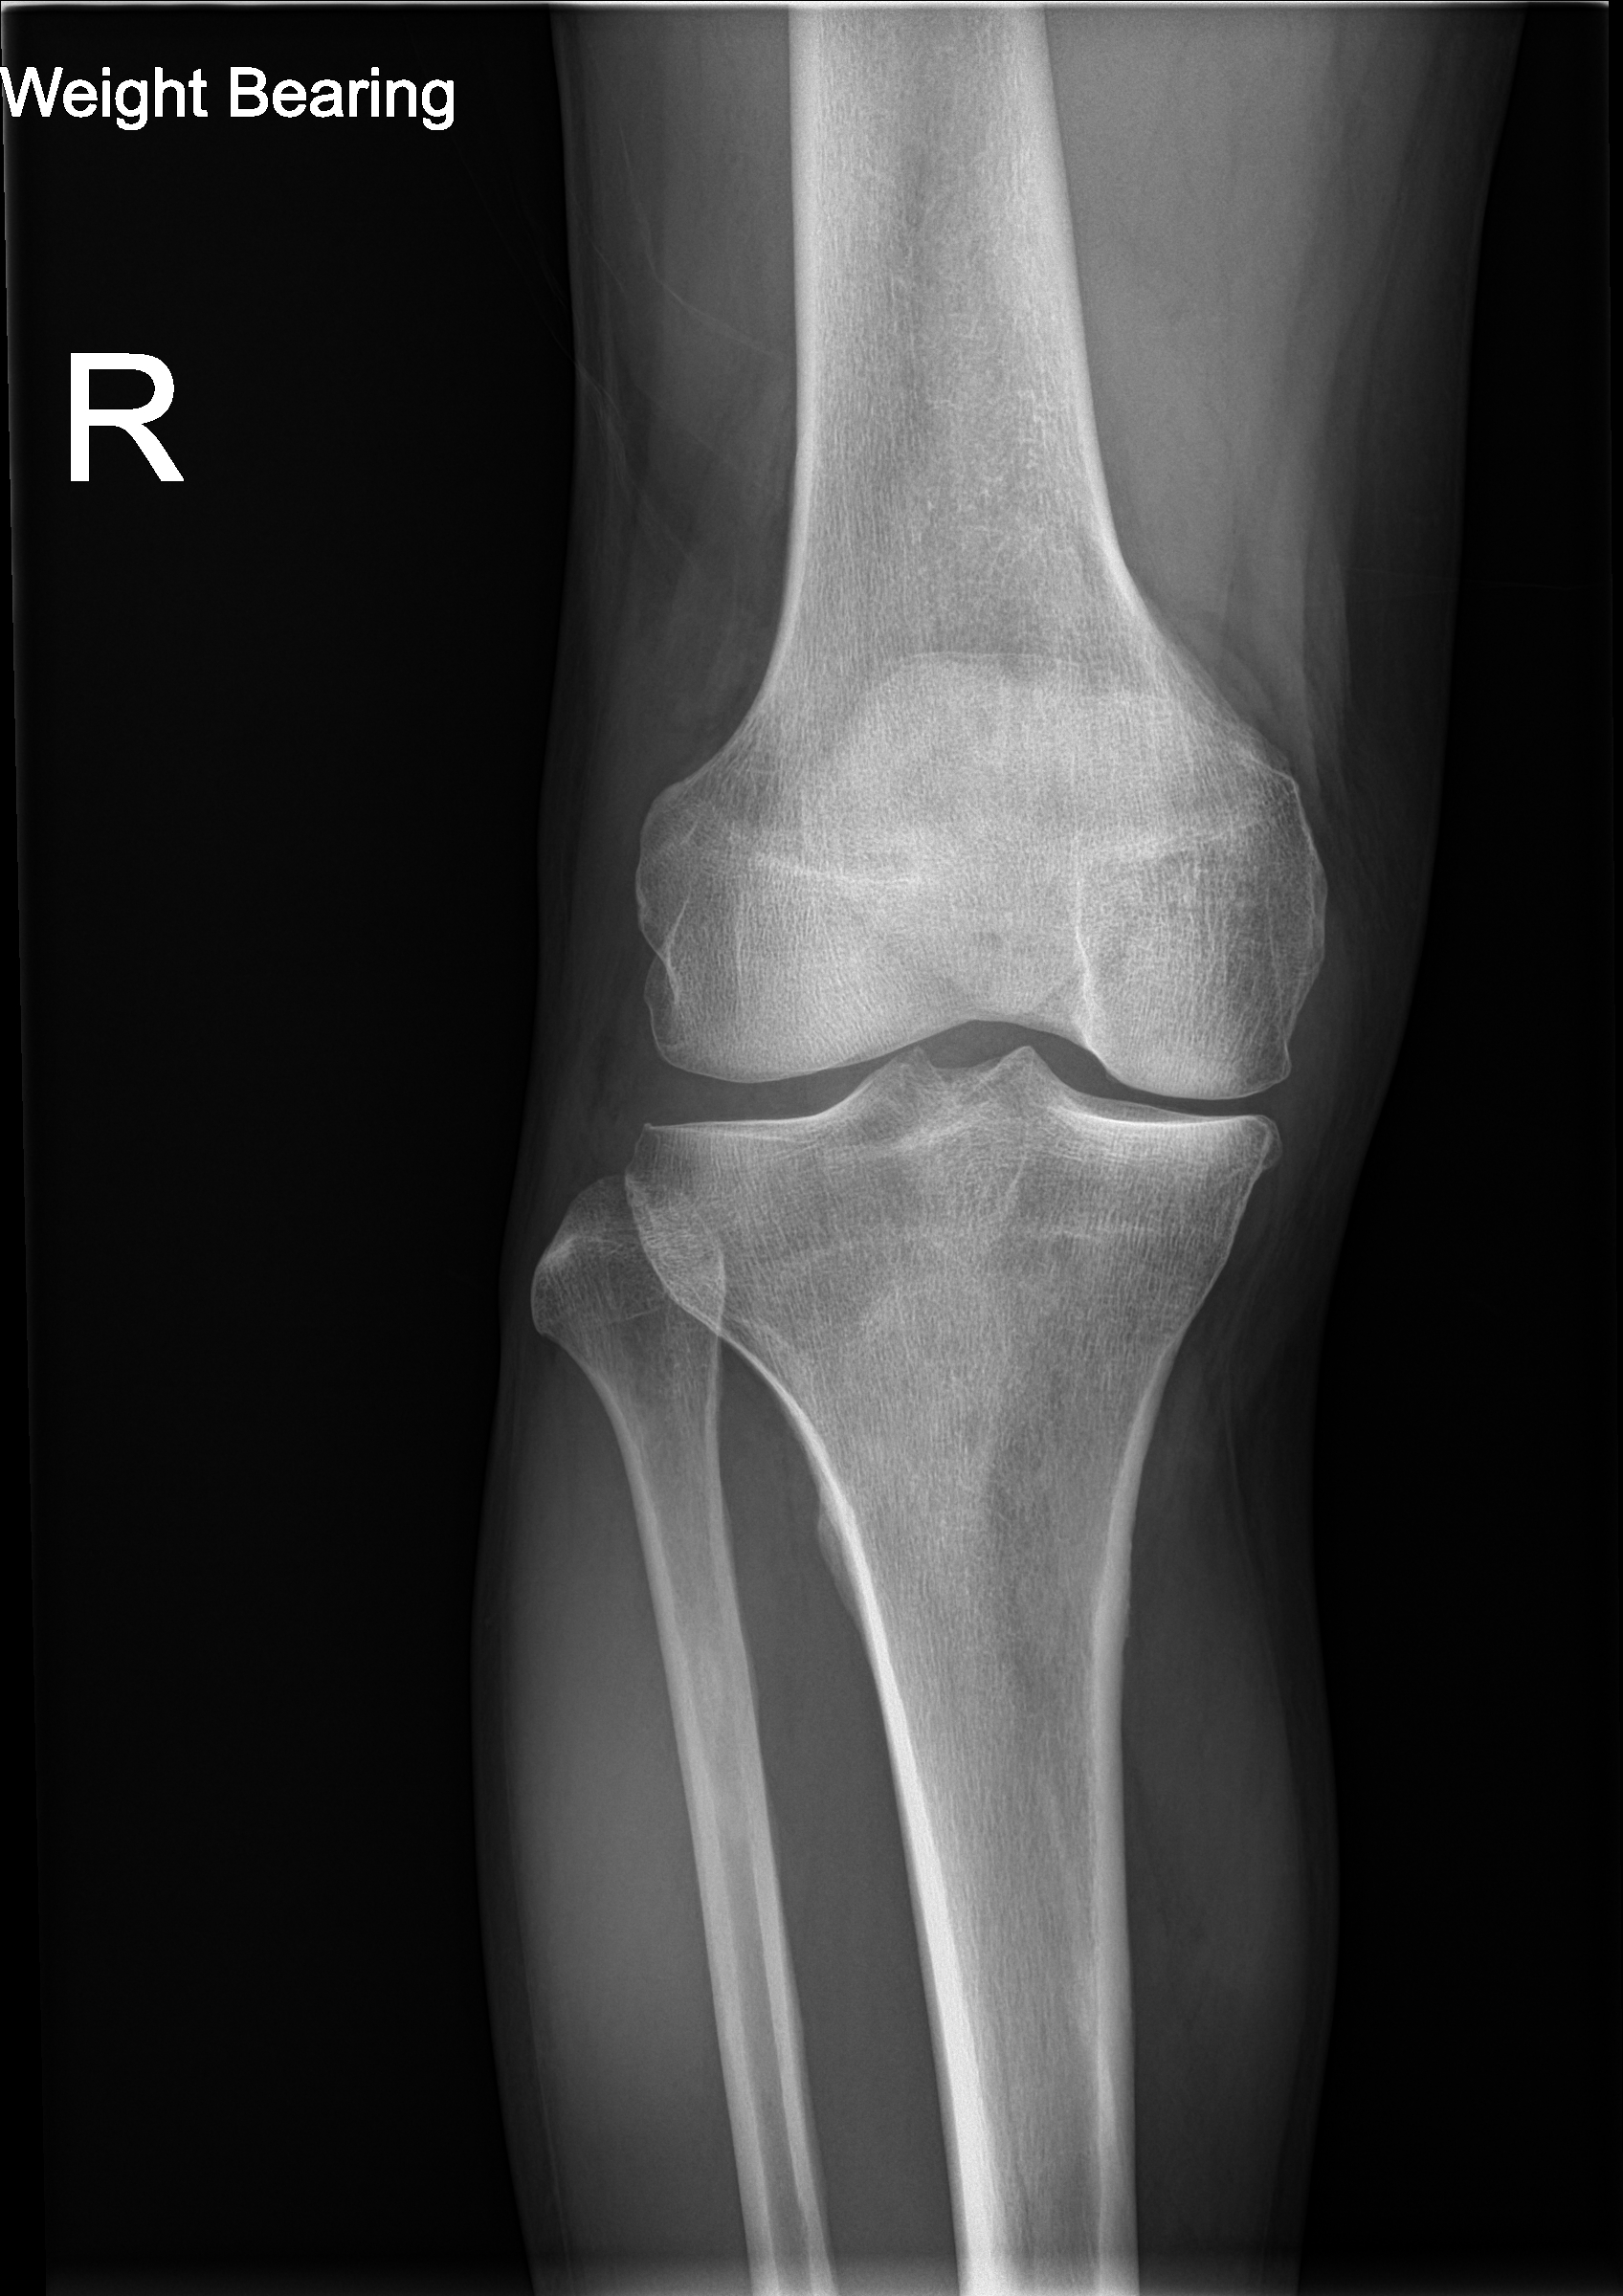

Diz kireçlenmesi

Diz kireçlenmesi; ağrı, tutukluk ve hareket kısıtlılığıyla seyreden, yaş, kilo ve eklem yüklenmeleriyle ilişkili bir hastalıktır. Muayene ve ağırlık taşıyan grafilerle tanı netleştirilir. Kilo kontrolü, egzersiz, ilaç ve eklem içi uygulamalar ilk basamaktır; seçilmiş hastalarda osteotomi, kısmi ya da total diz protezi ile kalıcı fonksiyon kazanımı hedeflenir.